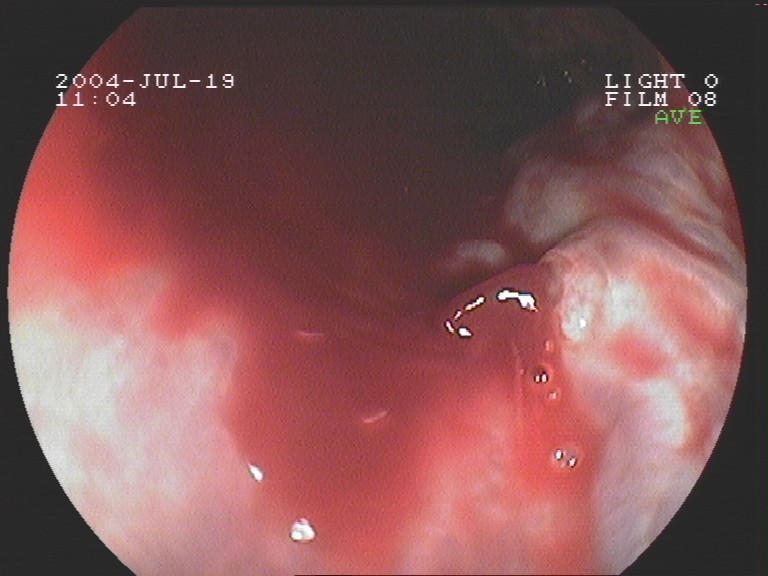

Gastroskopie - Ösophagusvarizenblutung